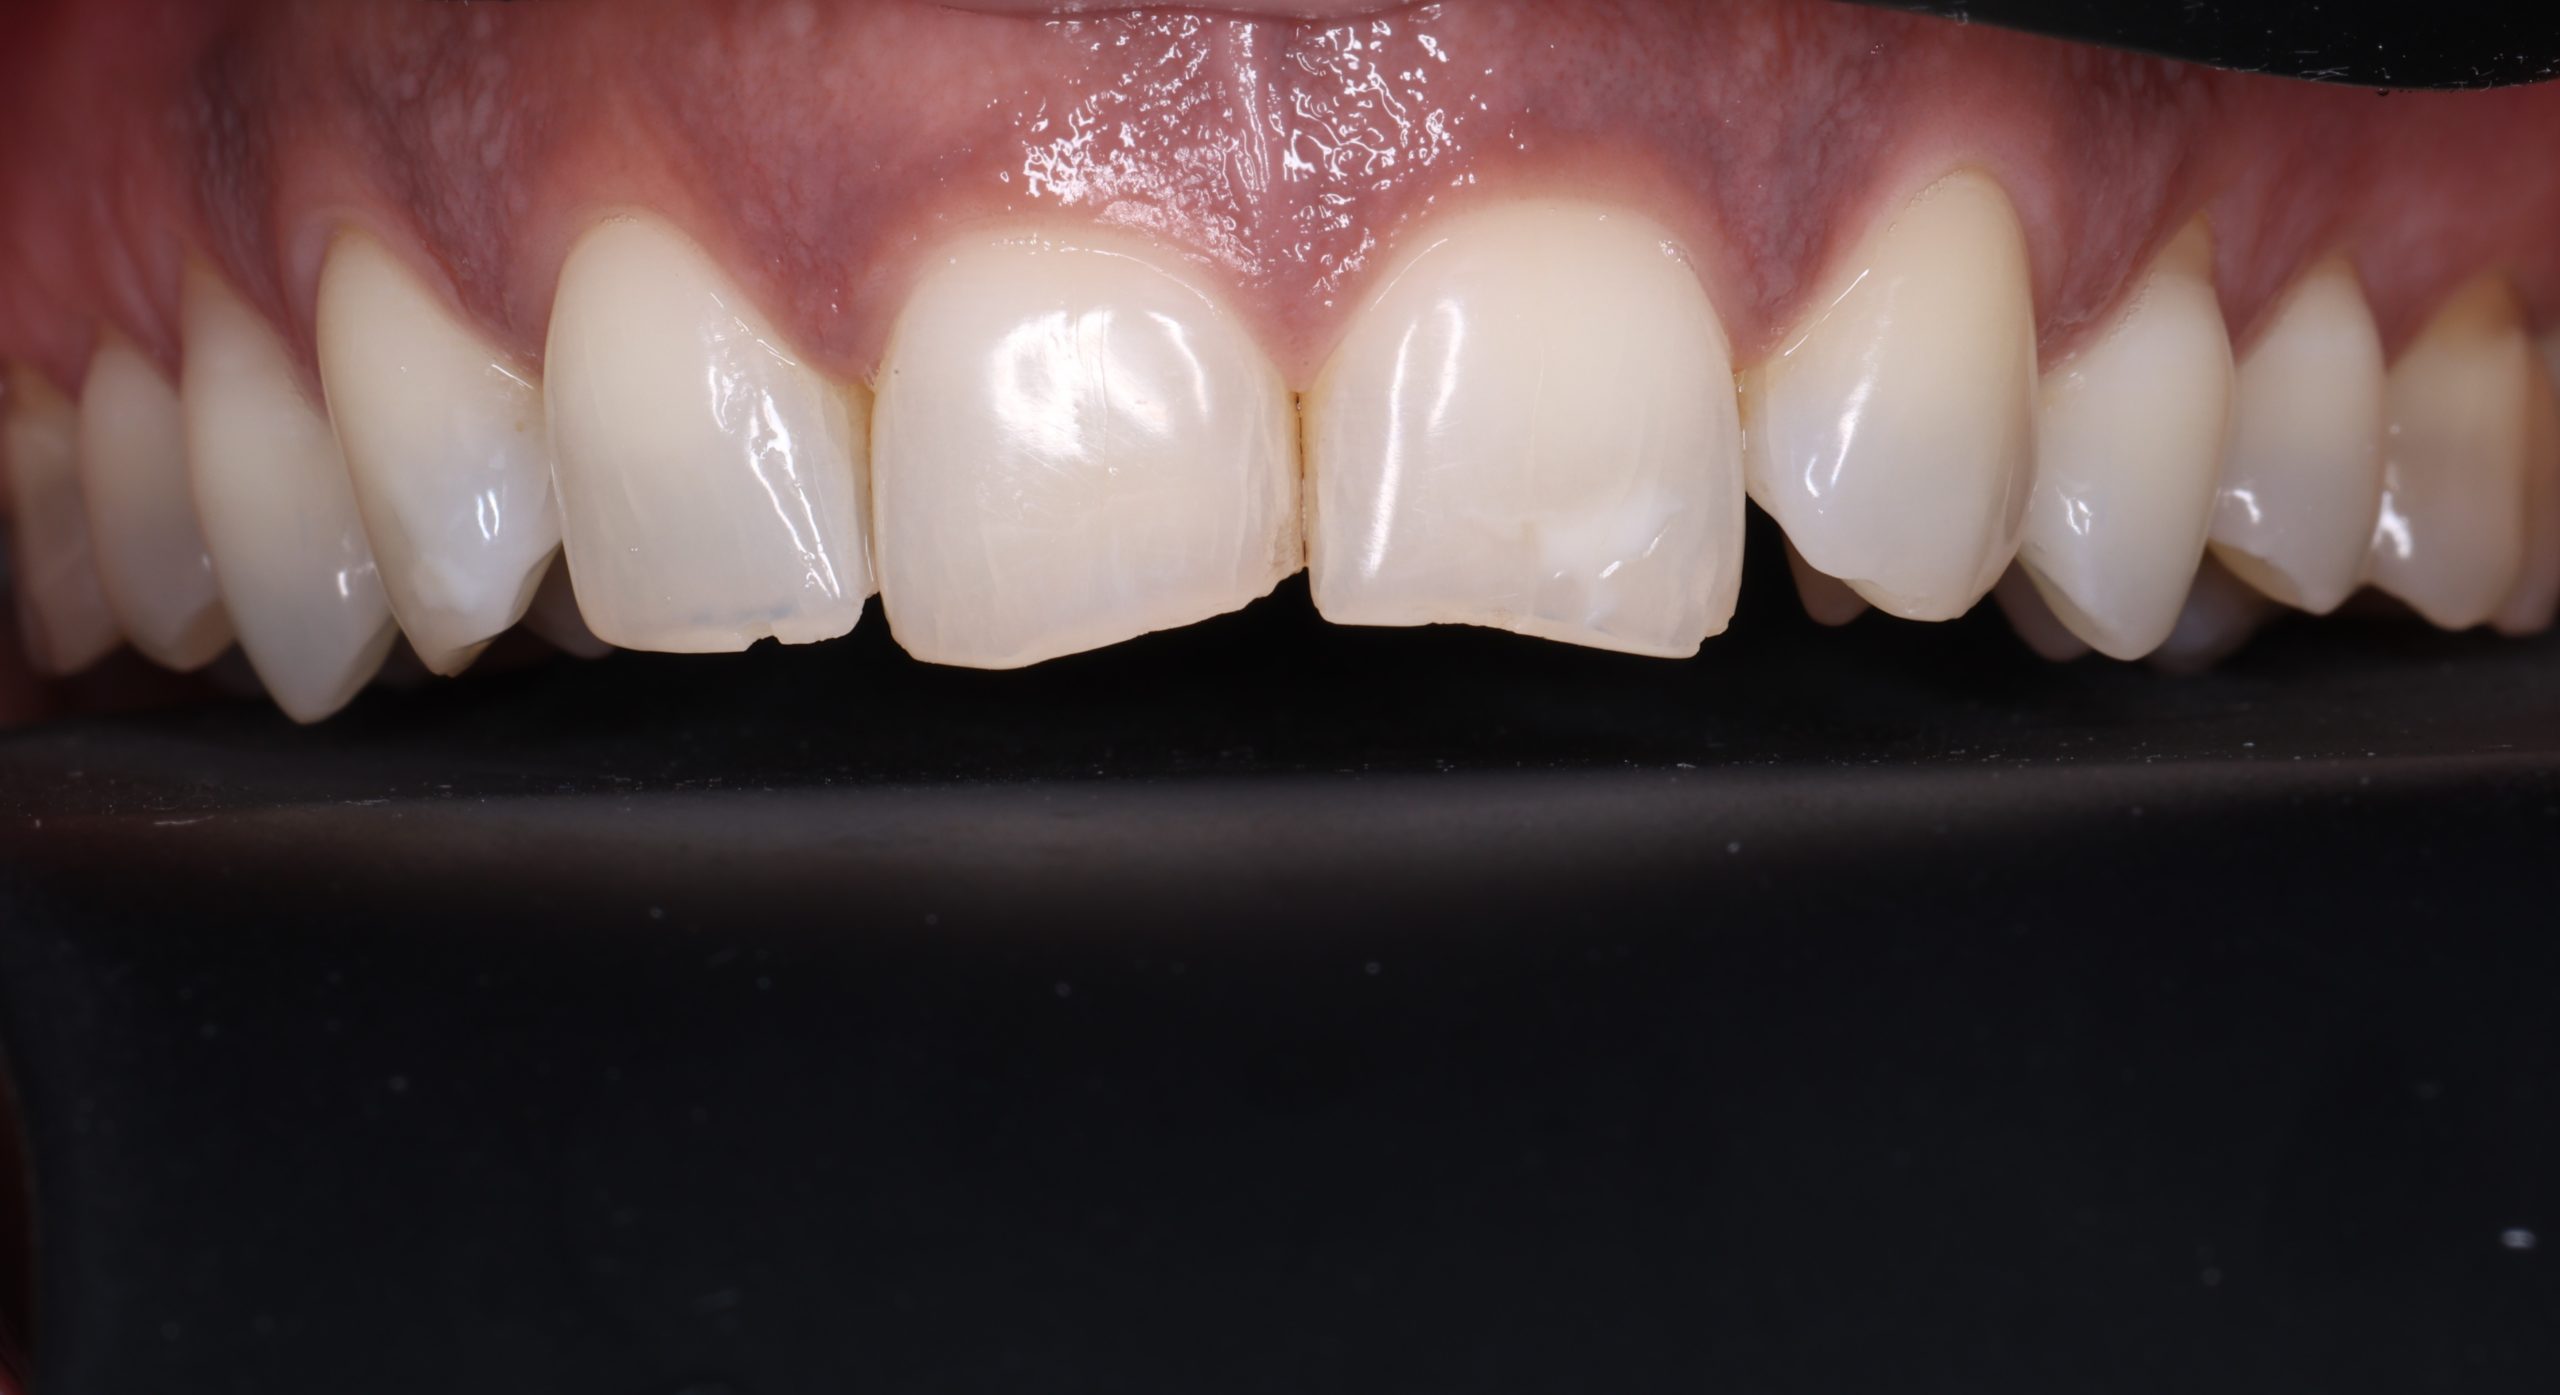

3. Layering the Composite Resin

The tooth-coloured resin is applied in thin layers and shaped carefully to match natural anatomy. For front-tooth work, we may combine several shades for a lifelike result.

5. Final Polishing and Bite Adjustment

We contour and polish the surface to a high gloss and ensure your bite feels natural in all positions.

Aesthetic and Natural-Looking

The material matches your enamel, blending into the smile with virtually invisible transitions.